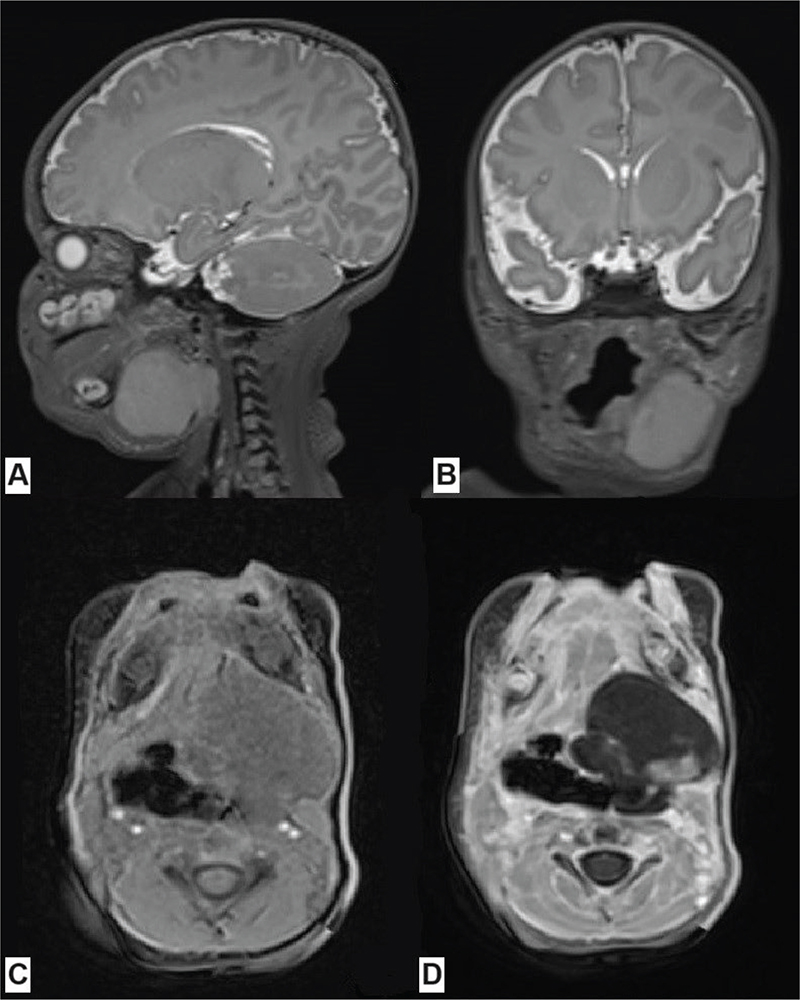

A 3-week-old infant presented with a tumor on the left submandibular region. The baby was born healthy and the pregnancy had been uncomplicated. He did not have a family history of cancer. The tumor caused asymmetrical positioning of the tongue and distorted the palate. When turning his head to the right, the boy presented upper-airway dyspnea. A craniofacial MRI showed a polycyclic, irregular mass of 3.6 × 3.4 × 3.0 cm in the left submandibular region extending to the oropharynx and to the supraglottis (Figure 2). Abdominal and thoracic CT and PET scans did not show any distant metastases. According to the CWS Guidance 2014 Protocol, the patient was classified to the standard risk group, of any histology, N0, IRS Group III, of ≤ 5 cm (however, due to the high-grade tumor, the patient was stratified and treated as the high-risk group). A biopsy was taken, and histopathological examination showed large cells with bright, granular cytoplasm. Immunohistochemistry showed the tumor to be negative for CK AE1/AE3, EMA, ALK1, CD20, CD30, glipican3, CD117, LCA, PLAP, inhibin, desmin, INI1, MelanA, SOX10, S100, synaptophysin, GFAP and CD34, while positive for SATB2, BCL6 corepressor (BCOR), ERG, CD99 and FLI1. Due to the unclear histopathology results, a genetic study using the FusionPlex Sarcoma v2 panel from tumor DNA was performed. In the meantime, a tracheostomy was performed as the tumor was obstructing the airways. As the tumor progressed, vincristine and cyclophosphamide-based chemotherapy was started, although the final histological diagnosis was still lacking. Taking into account the clinical presentation of the tumor and the child’s age, a decision was made to implement chemotherapy for soft tissue rhabdoid tumors according to Eu-Rhab regimen with good tolerance. A day after the third course of chemotherapy using vincristine, anemia and painless jaundice developed. Laboratory findings showed anemia grade 3 and thrombocytopenia grade 4 as well as grade 4 increase of serum bilirubin levels and transaminases, according to Common Terminology Criteria for Adverse Events (CTCAE). Hepatitis serology showed negative results for HBsAg, antiHBs, and antiHBc, as well as CMV-DNA and EBV-DNA were negative. In the course of differential diagnostics hemolysis, hemophagoctic lymphohistiocytosis and other conditions were ruled out, and finally fulminant toxic liver failure, probably induced by vincristine, was diagnosed. Despite hepatoprotective and empirical antibiotic treatment, liver failure progressed rapidly, and hepatic encephalopathy developed. Because of further deterioration of general condition mainly related to hepatic and respiratory failure, the patient was transferred to the pediatric intensive care unit (PICU). Further significant increases in aminotransferases and bilirubin, as well as abnormalities in the coagulogram, were observed. Due to kidney failure, renal replacement therapy was implemented. Nevertheless, in the following days, the patient’s condition continued to deteriorate and he deceased on the 7th day after PICU admission. NGS results obtained after the patient’s death revealed undifferentiated sarcoma with BCOR-internal tandem duplication (BCOR-ITD).

Figure 2. Craniofacial MRI of patient #2 at the time of diagnosis showing the tumor in the left submandibular region, modeling and displacing the left salivary gland, the styloglossus muscle, the posterior belly of the digastric muscle, the root of the tongue, the muscles of the mouth floor, the oral and laryngeal parts of the pharynx, and downwardly reaching the level of the middle part of the larynx: (A) T2 SPACE sequence (sagittal), (B) T2 SPACE sequence (coronal), (C) T1 VIBE sequence (axial), (D) T1 VIBE contrast enhanced sequence (axial). MRI: Magnetic Resonance Imaging.